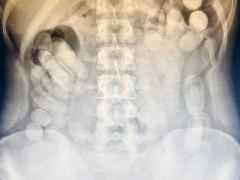

Radiografía evidenció las cápsulas ingeridas

Radiografía evidenció las cápsulas ingeridas Foto: Gendarmería Nacional

Radiografía reveladora y evacuación supervisada

Una vez ingresada al nosocomio local, la mujer fue sometida a estudios médicos para confirmar la magnitud del hecho. “Se le realizó una radiografía a la mujer mediante la cual se pudo observar la presencia de las dosis en su abdomen”, informaron fuentes oficiales. El procedimiento fue supervisado por personal médico y de seguridad.

Horas más tarde, en condiciones controladas, la involucrada evacuó un total de 106 cápsulas adicionales, lo que elevó la cantidad total a 118 envoltorios cilíndricos con aparente contenido de droga. La magnitud del hallazgo puso en evidencia el riesgo que implica esta modalidad de tráfico, tanto para la salud del portador como para la seguridad pública.